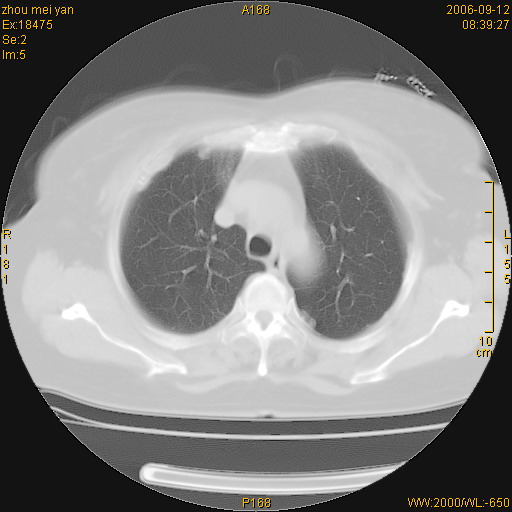

患者、女、55岁。因心率失常住院检查ct发现胸部多发结节。腹部b超肝、胆、胰、脾、肾、子宫附件未见异常。无结核病史,无粉尘接触史。请大家来会诊。谢谢!

病变位于胸膜,多发结节,边界清楚,内见小结节状钙化。其它未见异常。

多发胸膜表面的结节,基本对称,部分有钙化。首先考虑类风湿性胸膜结节,次则考虑结核性胸膜炎后遗之胸膜结节状增厚、钙化。

双侧胸膜多发结节,形态不规则,边缘较清楚,每一个结节中心似乎都有钙化点的特征,与胸膜广基相切。临床无结核病史,无粉尘接触史。

影像表现十分有特点:双侧肋胸膜及膈胸膜广泛散在分布大小在2至6mm左右,较大病灶中心可见钙化。

考虑恶性胸膜间皮瘤可能性大,病灶位于胸膜,以宽基地与胸膜相连,呈结节样改变,部分病灶内可见点状钙化影。请各位老师多多指导!

双侧肋胸膜及膈胸膜广泛散在分布大小不等结节影,较大病灶中心可见钙化。